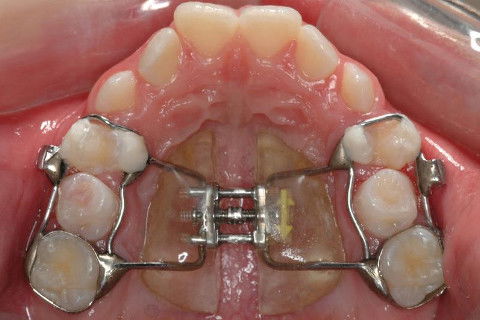

HAAS MULTIFUNÇÃO.

HAAS MULTIFUNÇÃO ATIVADO.

DIANTE DA QUALIDADE QUE O APARELHO APRESENTAVA PARA PROMOVER A EXPANSÃO RÁPIDA DA MAXILA O PROF. EDUARDO FRANCO PROMOVEU MODIFICAÇÕES DIVERSAS NESTE APARELHO;

CORREÇÃO SAGITAL;

CORREÇÃO VERTICAL;

CORREÇÃO TRANSVERSAL.